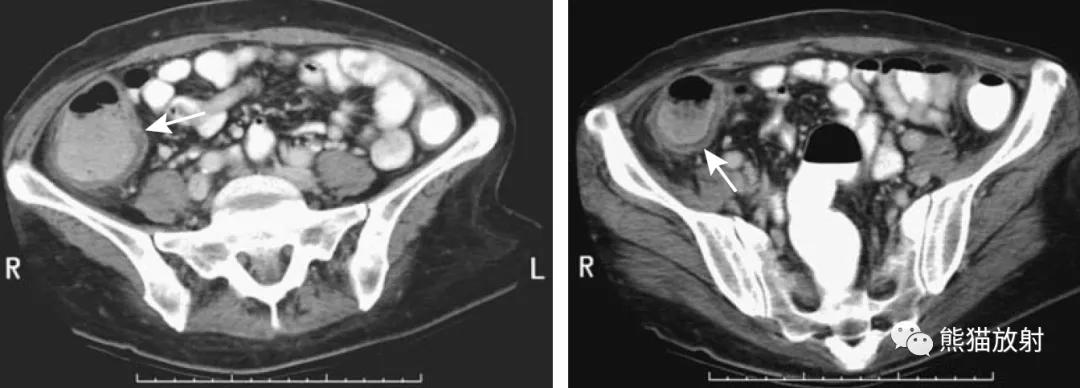

乙状结肠憩室炎。CT(A)和MR(B,C)图像。多发憩室,相应肠壁增厚、周围间隙混浊,不全肠梗阻。